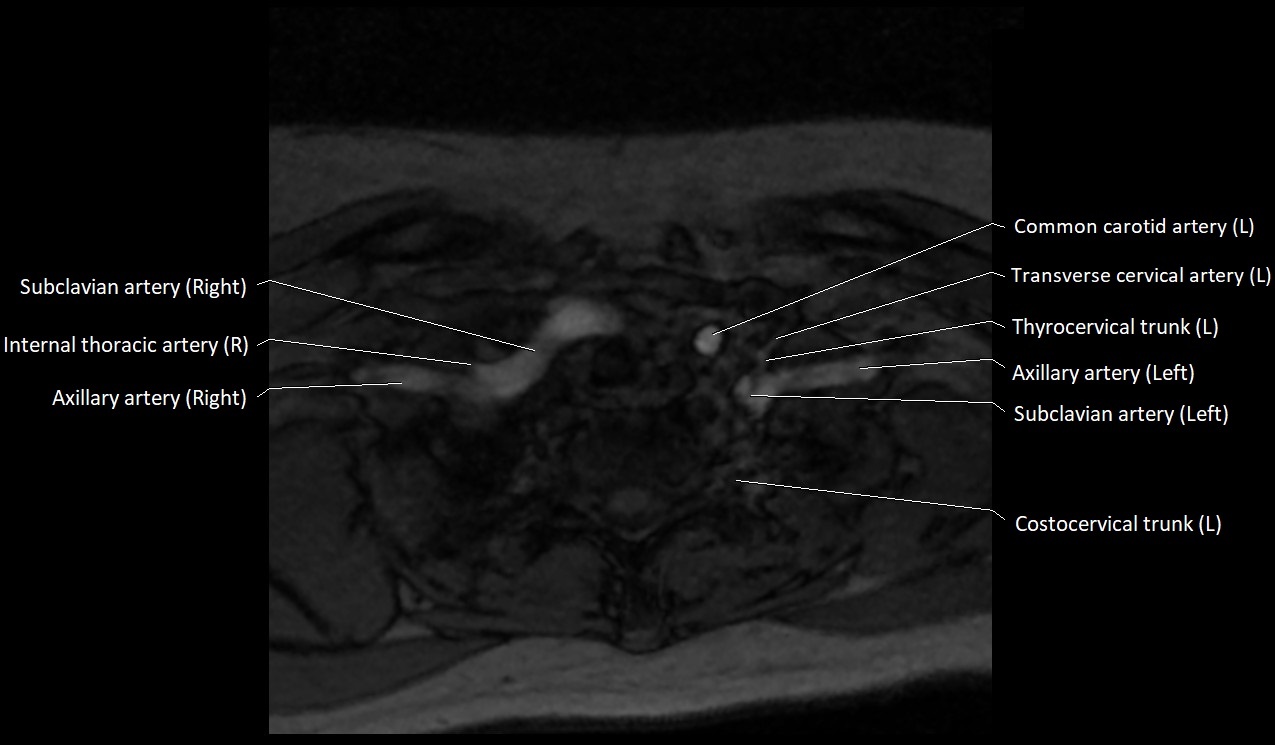

MRI images

image